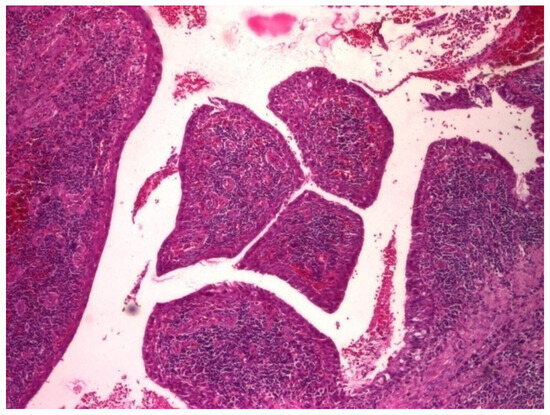

3.1.3. Analysis of Histopathologic and Immunohistochemical Results

| Histopathologic Aspects | Number of Patients |

|---|---|

| Cholesteatom | 276 |

| Polip | 180 |

| Tympanic membrane mucosa chamber, epithelium with apocrine-like cells, and chronic inflammatory infiltrate | 128 |

| Cell Types | Percentage |

| Lymphocytes T | 42.55% |

| Lymphocytes B | 31.45% |

| Macrophages | 26.00% |